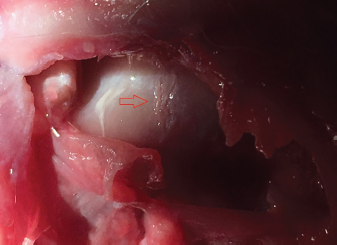

One shoulder experienced iatrogenic damage during the bicipital transection; partway through the procedure, the first researcher realized the needle was angled cranially rather than perpendicular to the long axis of the humerus. The needle angle was corrected and the procedure was completed successfully, but upon dissection it was determined that the cartilage surface of the humeral head had multiple full thickness lacerations (Fig. 7). Additionally, there was a 2–3 mm laceration of the medial aspect of the supraspinatus tendon (Fig. 8). Superficial scoring of the cartilage of the bicipital groove by the tip of the needle was evident in all shoulders at the level of the transection.

Fig. 7. Iatrogenic laceration of the cartilage of the humeral head (red arrow).